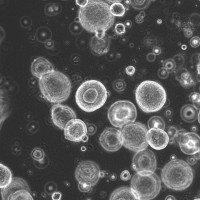

Salo Ooft and colleagues created a new strategy that uses organoid models of a patient's own tumour to predict how their cancer might respond to chemotherapy drugs.

They gathered samples from 61 patients with metastatic CRC and used the tissue to generate organoids, which they treated with irinotecan either alone or in combination with the chemotherapy 5-FU.